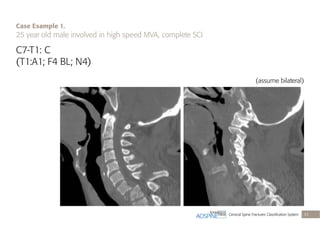

C7-T1: C

(T1:A1; F4 BL; N4)

(assume bilateral)

Case Example 1.

25 year old male involved in high speed MVA, complete SCI

Translational injury (C), with compression fracture

at T1 (A1), bilateral facet dislocations (F4 BL),

complete SCI (N4)